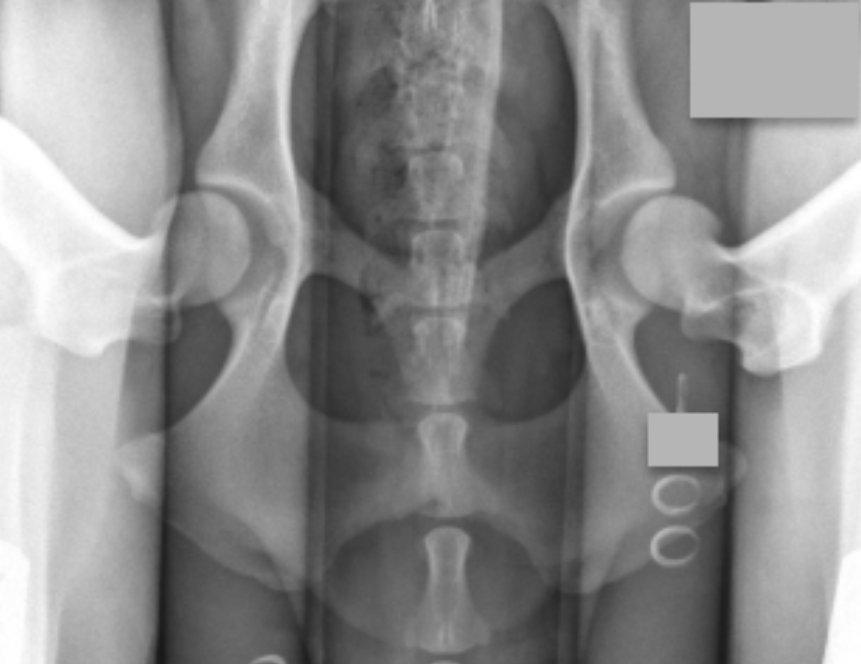

The PennHIP method accurately assesses, measures, and interprets hip joint laxity. Contrary to the singular, subjectively scored, conventional hip-extended radiographic view used by hip screening systems globally, the PennHIP method consists of three separate radiographs — the distraction view, the compression view, and the hip-extended view — and is shown to be a more accurate and better predictor for the onset of OA.

The distraction view and compression view are used to obtain accurate and precise measurements of joint laxity and congruity, respectively. The hip-extended view, sometimes called the OFA view, is used to obtain supplementary information regarding the existence of OA of the hip joint.

The radiographs pictured here are of the same dog, yet the hip joint laxities in each view look very different. Notice that the hips in the distraction view with the hips positioned in a neutral weight-bearing orientation appear to be much looser than they do in the hip-extended view.

The obvious contrast in joint laxity between the distraction and hip-extended views demonstrates the fundamental difference between the two radiographs. The looser the joint on the distraction view, the greater is the chance that the hip will develop OA. The hip-extended view tends to mask true hip joint laxity because the joint capsule is wound up into a tightened orientation when the hips are extended. This explains why measurable joint laxity on the distraction view is always greater than the measurable laxity from the hip-extended view. In fact, distraction laxity can be up to 11 times greater, depending on the breed of dog under study.